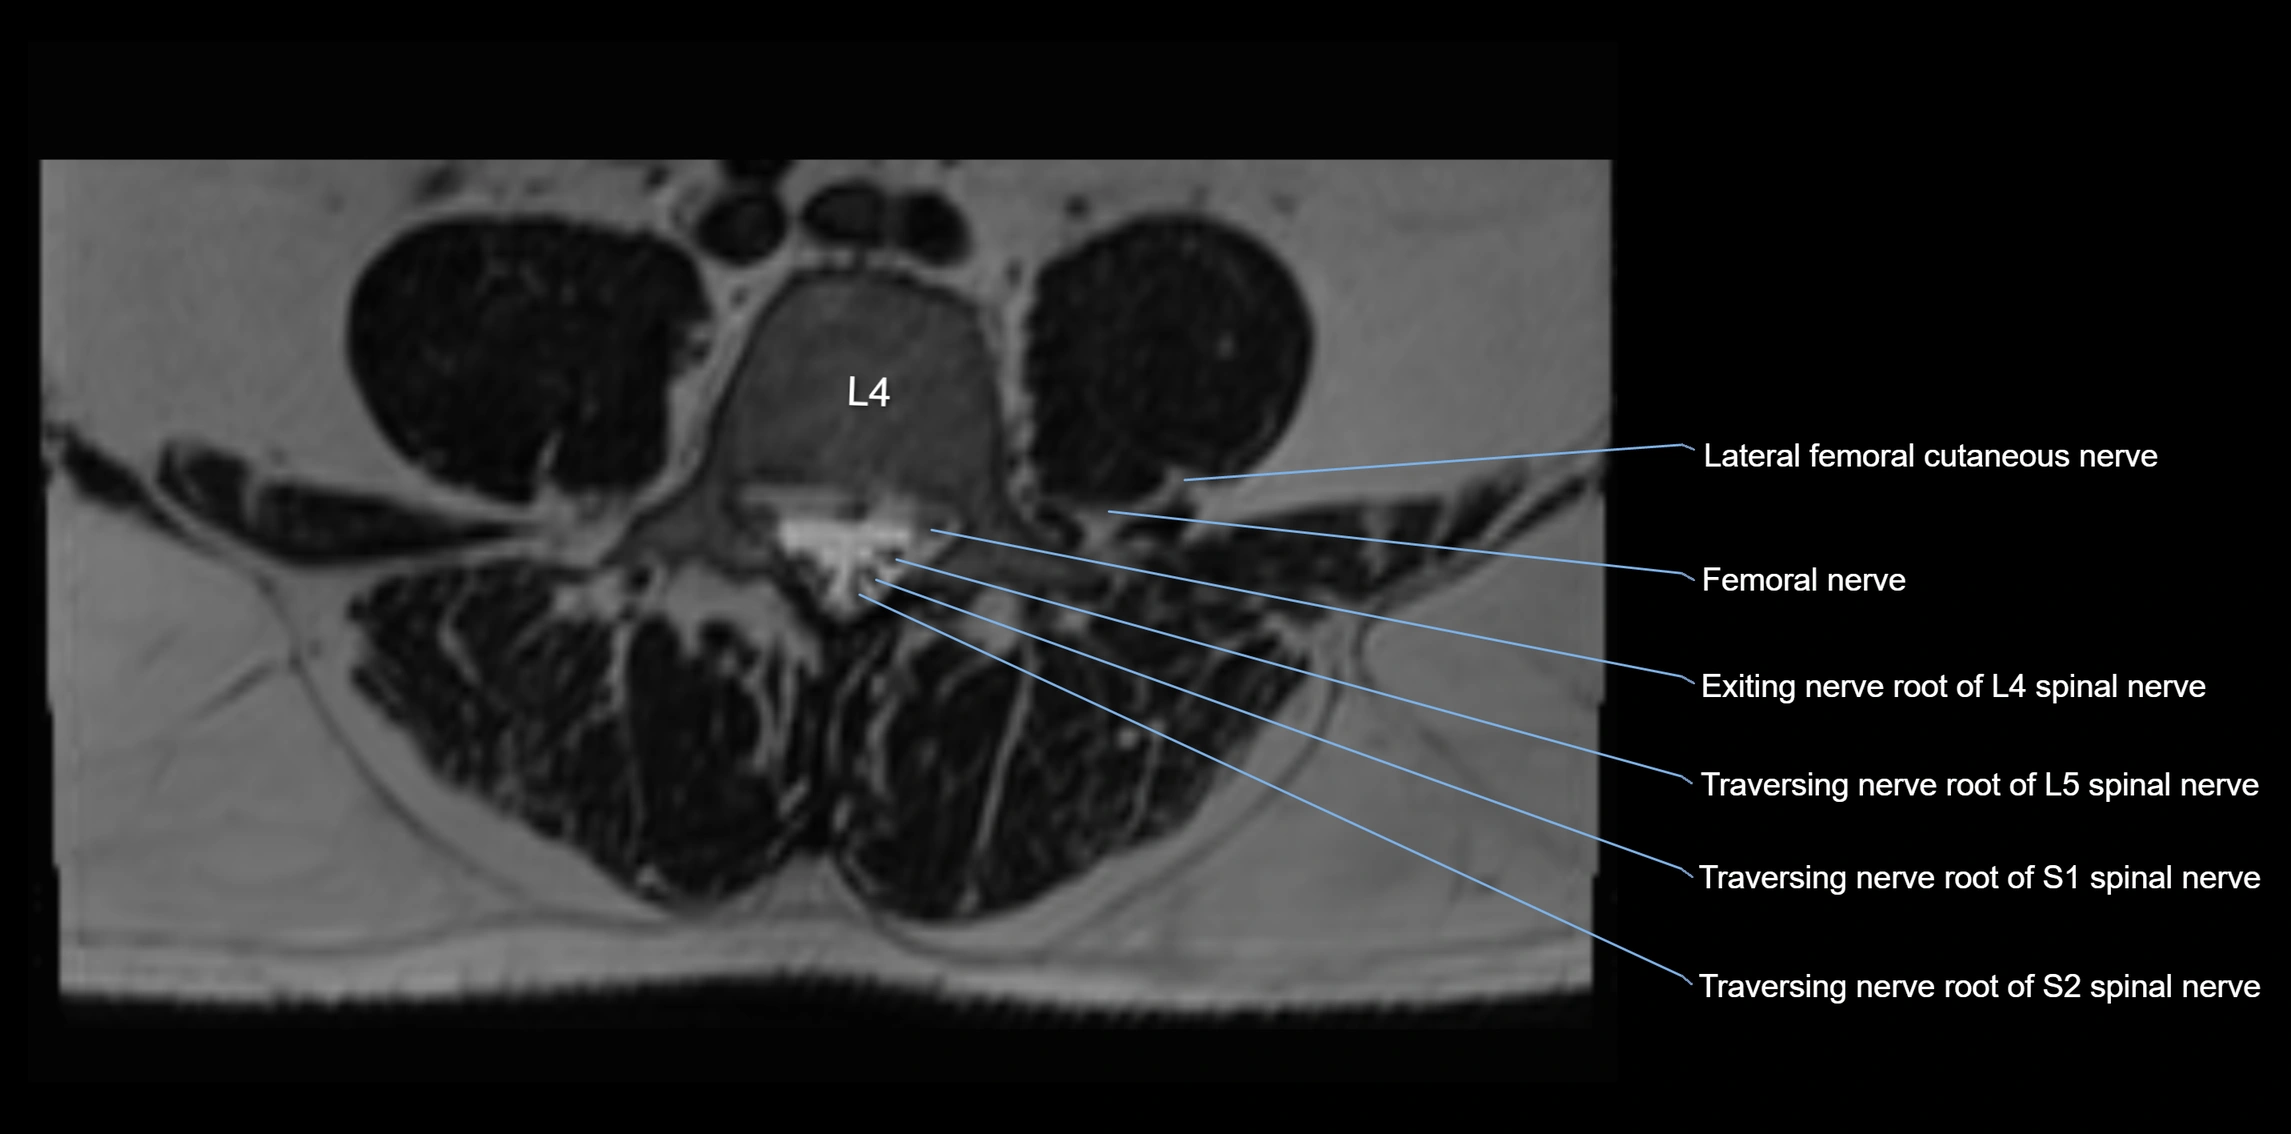

MRI image

image